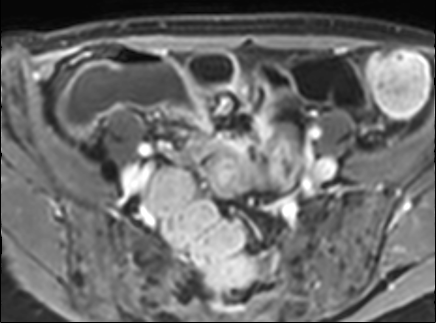

Thâm nhiễm

Thâm nhiễm có thể biểu hiện dưới dạng mỡ bò (creeping fat) xâm lấn giữa các quai ruột kèm thay thế tín hiệu mỡ bình thường, cùng với hiện tượng kéo dính và gập góc các quai ruột.

Các triệu chứng tắc nghẽn do dính ruột, hẹp do viêm hoặc xơ hóa là những biểu hiện thường gặp.

Rò và áp-xe thường đồng thời hiện diện.

Do cấu trúc phức tạp, đường đi chính xác của đường rò có thể khó xác định.